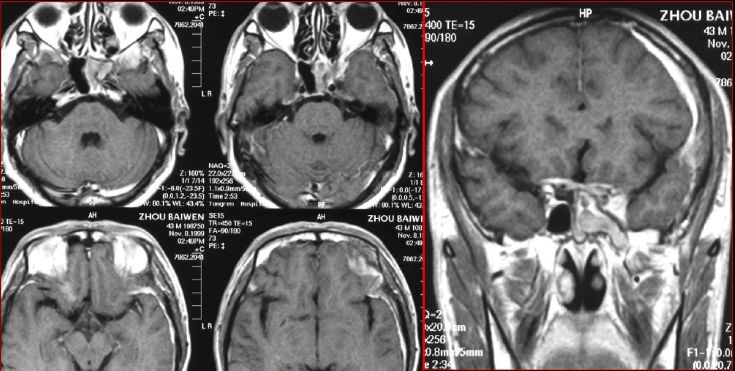

慢性多发鼻窦炎—MRI